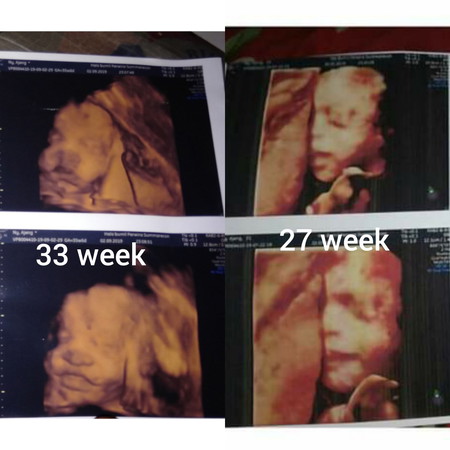

Beby boy

?? perubahan nya Beby boy 27 ke 33 week

lebih berisi